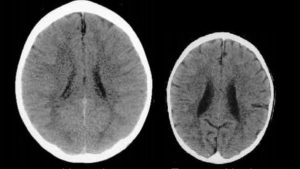

ألقِ نظرةً على صورة الدماغين في الأسفل. بالرغم من أنّها تعود لطفليْن من نفس العمر، ستُلاحظ أنّ الدماغ على الجهة اليسرى من الصورة أكبر وببنيات أقلَّ تشوشا مقارنة بالدماغ الموجود على الجهة اليمنى من الصورة.

مصدر الصورة: http://citeseerx.ist.psu.edu/viewdoc/download?doi=10.1.1.115.6208&rep=rep1&type=pdf و http://www.iflscience.com/brain/images-show-the-shocking-effect-of-emotional-trauma-on-a-childs-brain/

سببُ هذا الاختلاف الجِذري ليس راجعا لمرضٍ أو لإصابةٍ جسدية، بل هو في الواقع راجع لصدمة عاطفية شديدة وأيضا للإهمال. الصورة مأخوذة من ورقة بحثية قدّمها البروفيسور Bruce D Perry، رئيس قسم الطب النفسي في مستشفى تكساس للأطفال.

” الأشعة المقطعية على اليسار هي صورة لدماغ طفل بصحّة جيدة يبلغ من العمر ثلاث سنوات بحجم رأس متوسط، صورة الدماغ على يمين الصورة تعود لطفل يبلغ من العمر ثلاث سنوات أيضا لكنّه يعاني من الحرمان الحسِّي و كذا الإهمال. هذا الدماغ هو أصغر بكثير من المتوسط، بِبُطينات واسعة و ضُمور قشرية “.